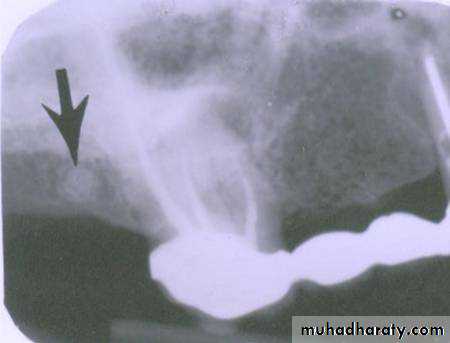

premolar filmThe arrow in the canine film is pointing to the gutta percha in which canal of the maxillary first premolar?

The arrow identifies the lingual canal. The tube head moves mesially from the premolar film to the canine film (beam directed more distally) and the gutta percha indicated by the arrow also moves mesially. (See following slide).

lingual

buccalWhen the tube head is moved mesially, with the beam directed distally, the two canals, which are initially superimposed (premolar periapical above) will separate. The lingual canal (red arrow) will follow the tube head movement and the buccal canal (blue arrow) will move in the opposite direction, as seen on the canine film.